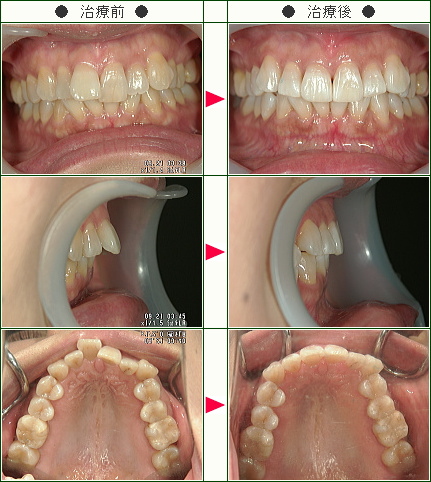

☆出っ歯矯正症例(M.I様 43歳 男性)

主訴は前歯の前突感の改善です。

まずはワイヤーを使用してデコボコを改善していきます。

ワイヤーの使用期間が約4か月で、マウスピースを3か月使用して歯並びを内側に傾斜して治療していきました。

トータルでの治療期間は7ヵ月で、調整料金を含めたトータルの治療費は29万円です。

上側だけの部分矯正では、噛み合わせは変わりませんので、見た目の改善だけの審美治療になります。

部分矯正において、ワイヤーでデコボコを改善するだけだと、矯正前よりも少しだけ前方に出てしまうため、歯の隣接面を少し削ることで前歯の前突感を改善していきます。

どこまで前歯を中に入れたいかで、隣接面を削る量は患者様の判断で決まります。

また歯を削らないでデコボコを治すだけですと、デコボコのある間にブラックトライアングルという隙間も残るため、ブラックトライアングルを減らすという目的のためにも前突感を改善するためにもその部分の隣接面を削って内側へ入れていきます。